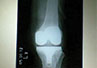

Case 8: Total Knee Replacement

Both knee osteoarthritis in a 62 years female.

Images

X-RAY 1

Both knee osteoarthritis

X-RAY 2

xray after both knee replaced